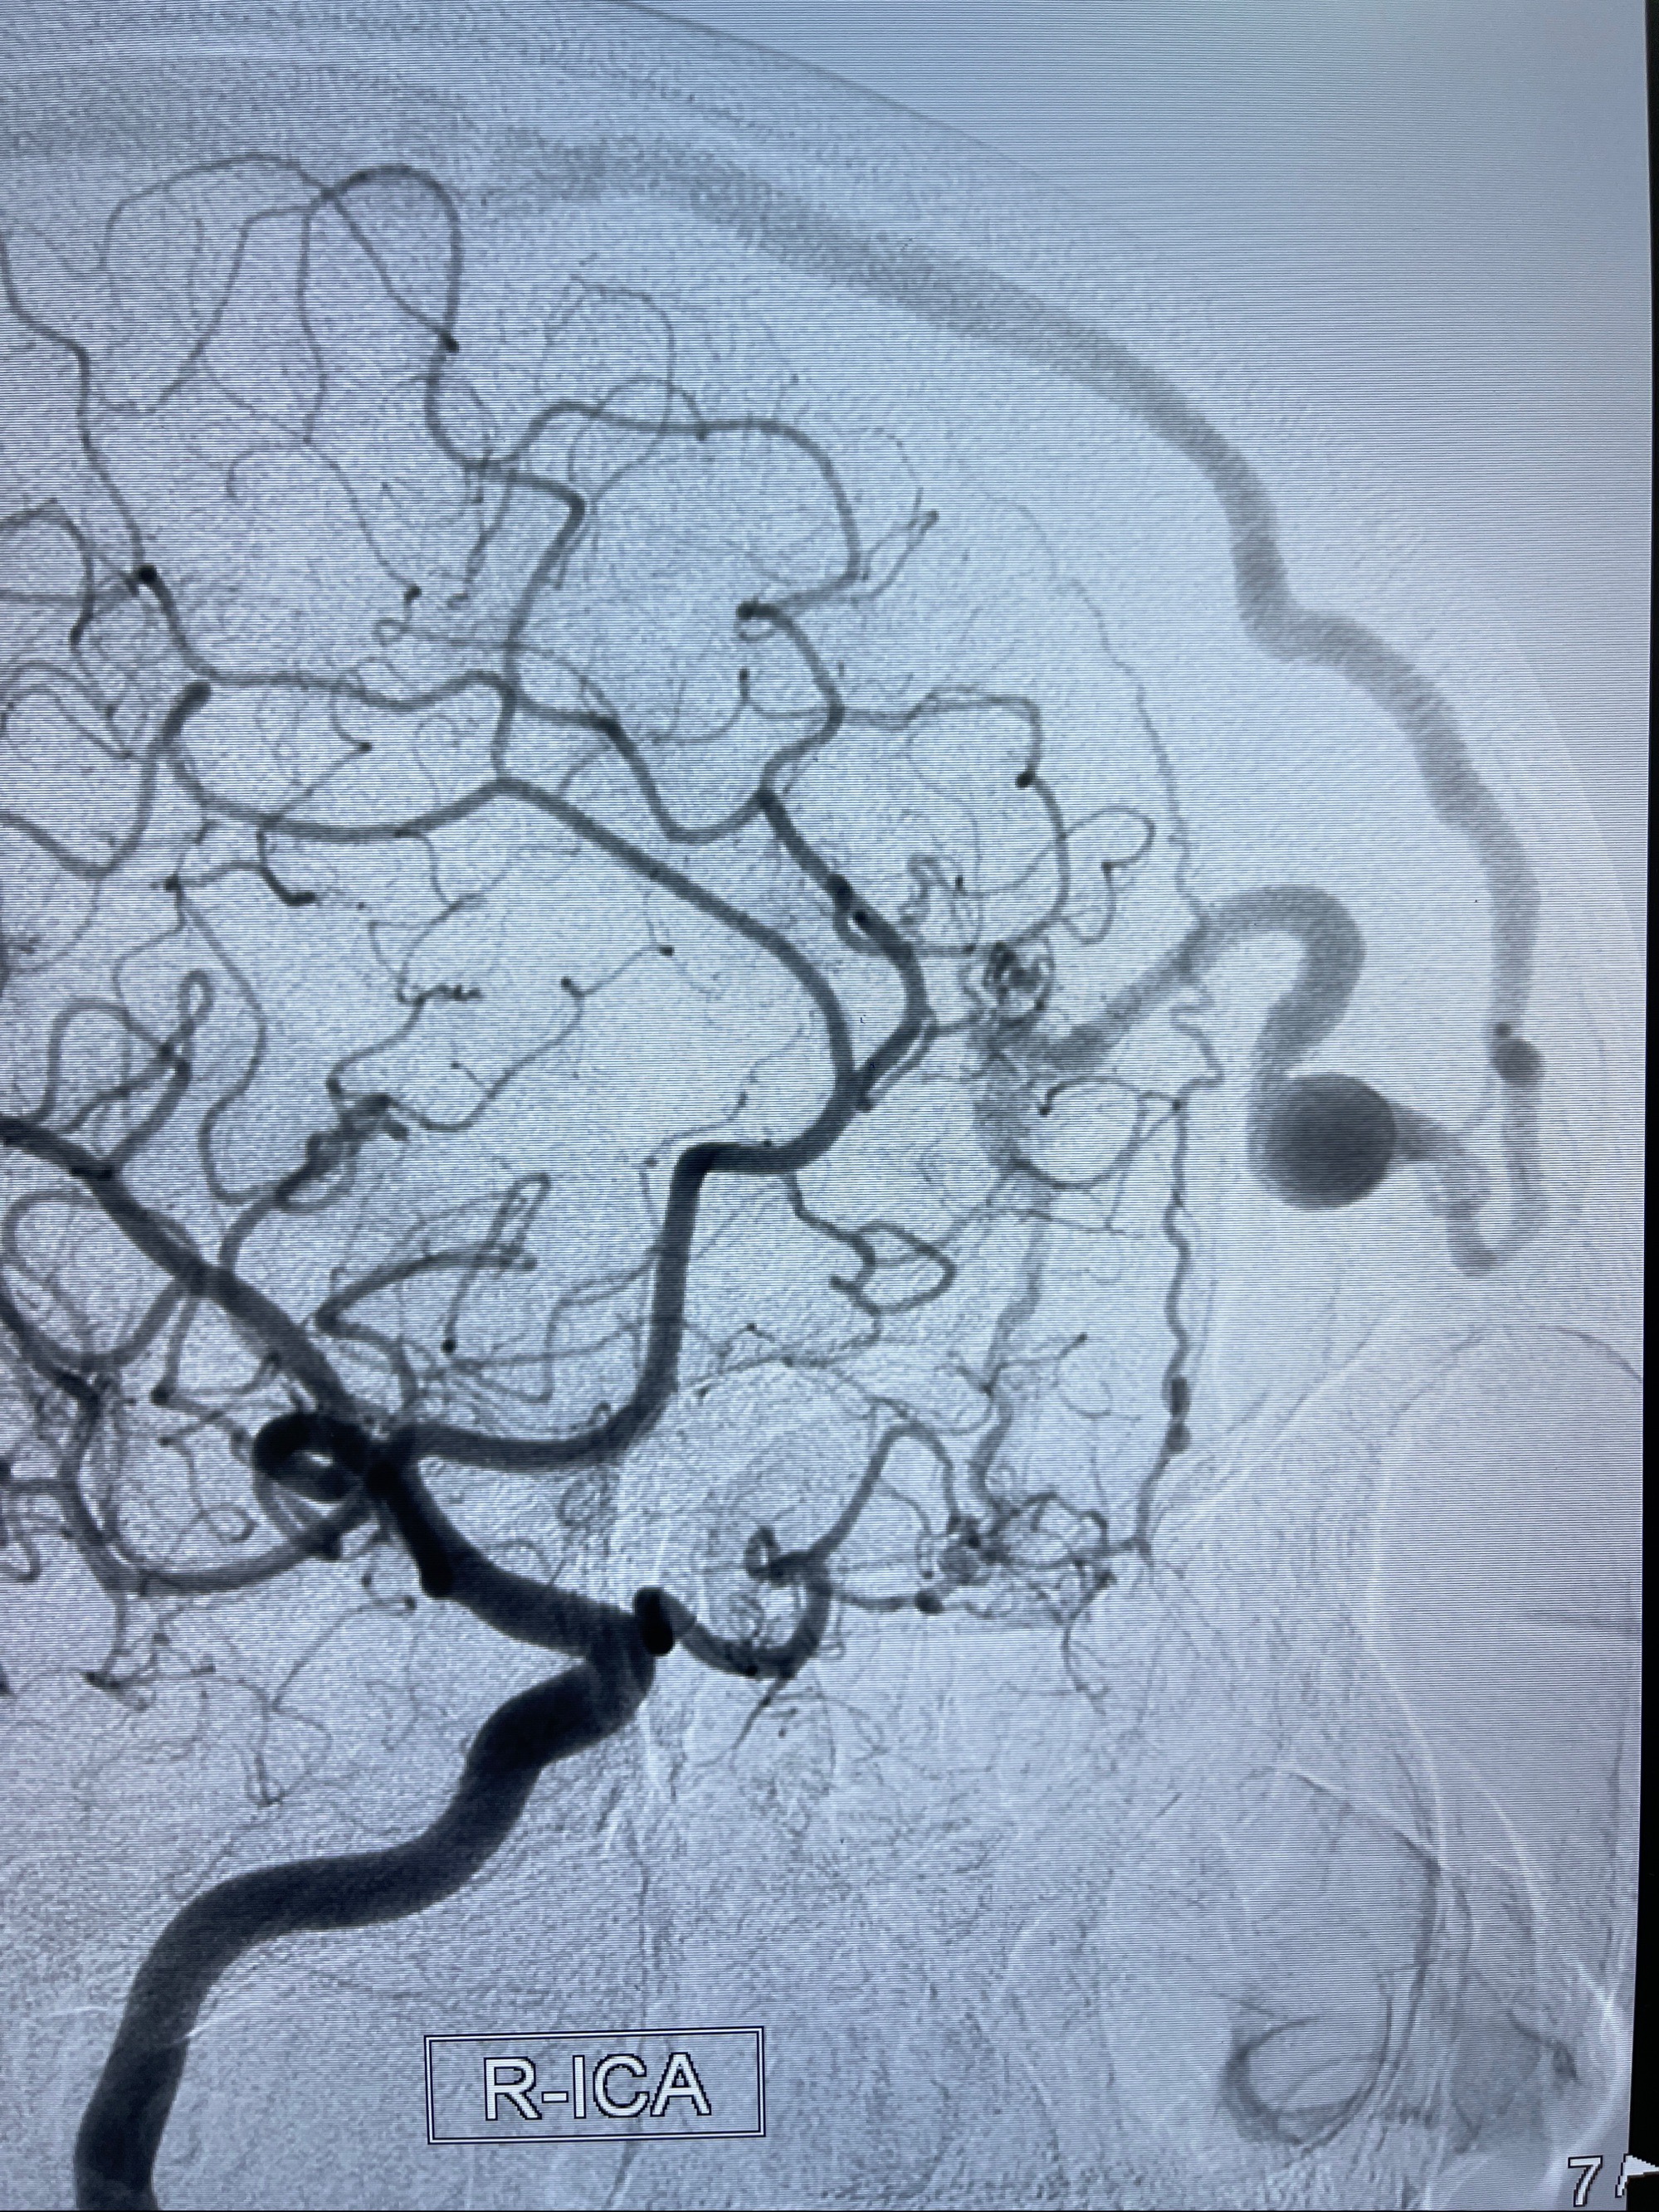

2023年8月21日]景德镇市第一人民医院脑血管造影检查,提示:主动脉弓、双侧颈总动脉、锁骨下动脉造影未见异常,左侧大脑前动脉静脉瘘。

2023-09-13全脑血管造影:前颅底硬脑膜动静脉瘘,供血动脉为双侧胼周动脉、眼动脉脑膜支,静脉向上矢状窦方向引流

治疗策略:

- 外科手术?

- 介入干预:静脉途径栓塞or动脉途径填塞?